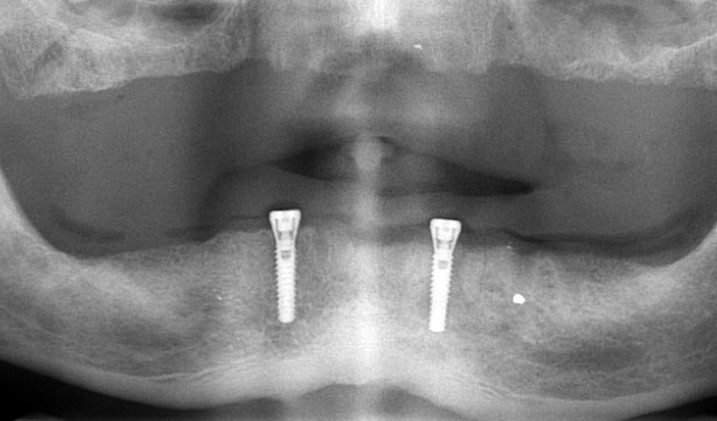

Tijdens de afspraak van het plaatsen van de implantaat hebben we de patiënt eerst verdooft. Voor het plaatsen van een implantaat wordt gewoon normaal verdooft zoals ook wordt verdooft voor het boren en vullen van een gaatje, want die verdoving verdooft alles: zowel het tandvlees als het daaronder gelegen bot. We hebben op de plaats van het gat een sneetje gemaakt. vervolgens hebben we met speciale implantaatboren een ’tunneltje’ geboord in het kaakbot. Vervolgens hebben we een speciaal titanium schroefje in het bot gedraaid. Door het gat van het tunneltje in het bot iets nauwer te laten zijn dan het te plaatsen implantaat, komt het implantaat bij het indraaien in het kaakbot al goed vast te zitten. Soms is deze primaire stabiliteit zo goed, dat er meteen een noodkroon op geplaatst kan worden. Zodra dan de echte kroon klaar is, kan deze meteen geplaatst worden en loop je

niet lang rond met een noodkroon.